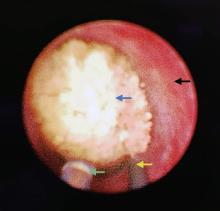

Figure 2

Photograph in RULL + N-trap The blue, green, yellow and black arrow respectively points at the calculus, the N-trap, the dual-flex guidewire and the wall of ureter. RULL + N-trap, rigid ureteroscopic laser lithotripsy combined with N-trap."